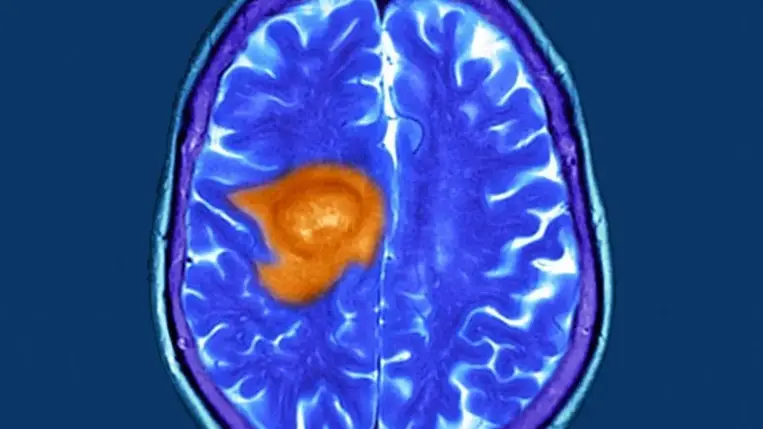

A glioblasztóma napjaink egyik legfélelmetesebb és legagresszívabb agydaganat típusa.